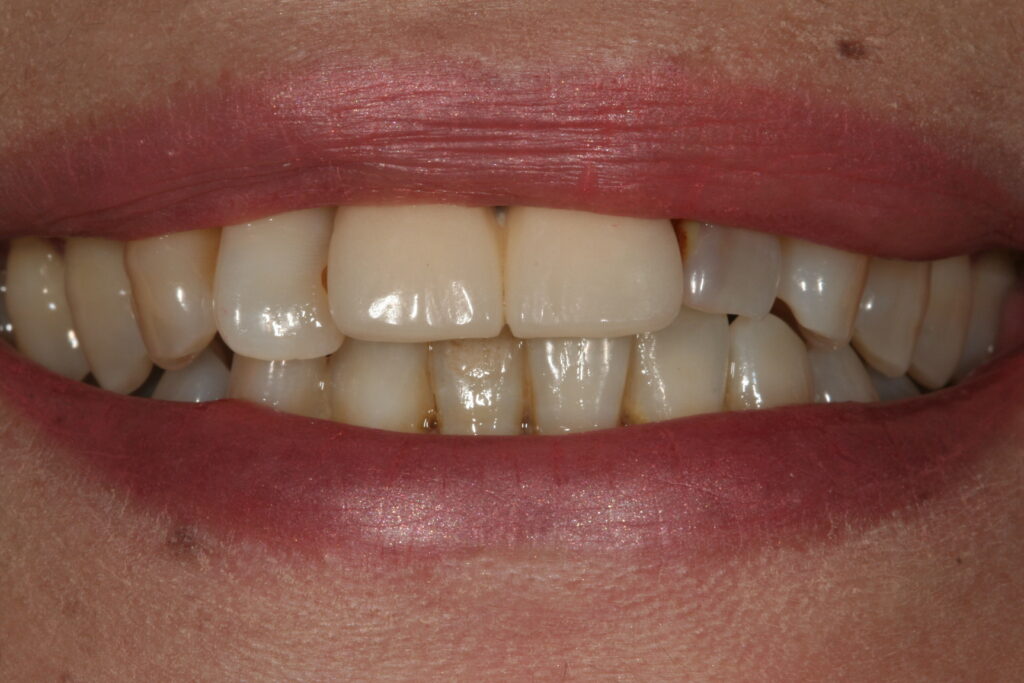

審美治療 2015.09.26 症例紹介 10年以上前から前歯の見かけが気になっておられました。1回目:カウンセリング2回目:治療、型取り、仮の歯3回目:取り付けて終了 でした。 症例紹介 都市伝説、、、、、前の記事 歯石とは?次の記事